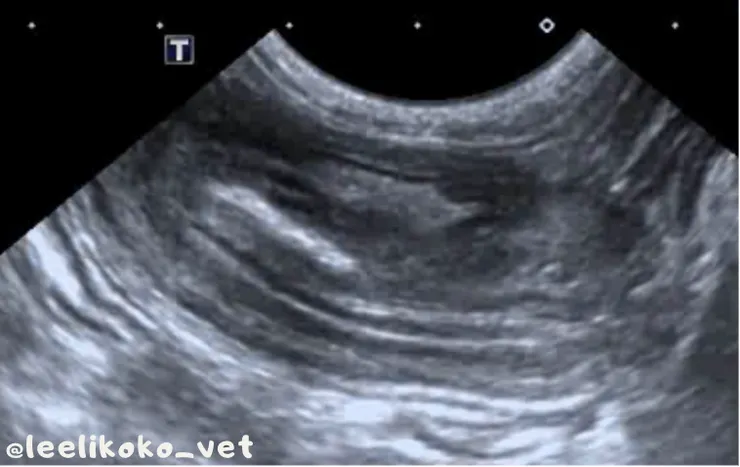

- 縱切面中可見多條高回聲與低回聲平行線

腹腔超音波- 腸套疊位置縱切面